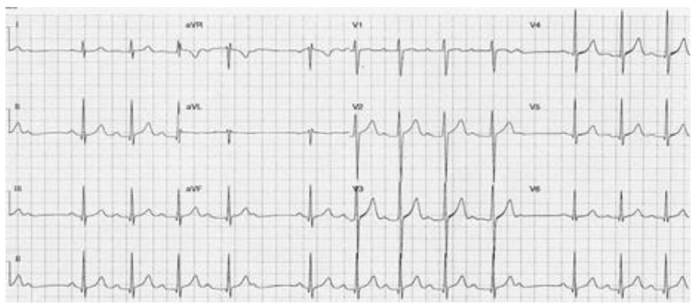

Mulher de 68 anos, com hipertensão e dislipidemia, foi atendida na emergência devido à dor torácica com 90 minutos de evolução. O

eletrocardiograma de admissão foi compatível com uma síndrome coronariana aguda com supradesnível de ST de parede inferior.

Encaminhada imediatamente à hemodinâmica e submetida à angioplastia com implante de stent no segmento proximal da coronária

direita com sucesso. Houve resolução da dor e do supradesnível do segmento ST, e não havia lesões residuais. Mantida dupla antiagregação

plaquetária, ao ser internada na unidade cardiointensiva seu eletrocardiograma revelou o traçado abaixo. No momento do registro a

paciente estava assintomática, com frequência cardíaca 70 bpm, pressão arterial 124x66 mmHg, e sem sinais de congestão pulmonar.